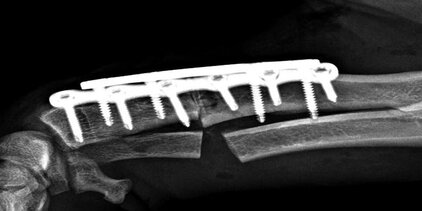

Kreuzbandriss — erkranktes Gelenk im Speziellen

Die häufigste Lahmheitsursache der Hintergliedmaße beim ausgewachsenen Hund und auch älteren Katzen ist ein Riss des vorderen Kreuzbandes, oft begleitet von einer Verletzung des inneren Meniskus. Kreuzbandrisse führen zu Instabilität, Meniskusfolgeschäden, Gelenksentzündung und Arthrosebildung im Kniegelenk. Bei einem Kreuzbandriss des Hundes liegt meist eine chronisch-degenerative Erkrankung zugrunde, weniger das scheinbar akute Trauma. Abhängig von Größe, Gewicht und Alter Ihres Tieres, sowie dem Verletzungs- und Arthrosegrad des Kniegelenkes empfehlen und führen wir die Meniskusdiagnostik und die für Ihr Tier angebrachteste Kreuzband-Operation durch. Die mit von uns weiterentwickelte, moderne TTA Rapid Methode zur Kreuzbandbehandlung mit dem Titan Implantat der Firma R.Leibinger medical bietet eine sehr frühe Wiederbelastung der operierten Gliedmaße und schnellere Genesung Ihres Hundes und Ihrer Katze.

- TTA Rapid® Tibial Tuberosity Advancement